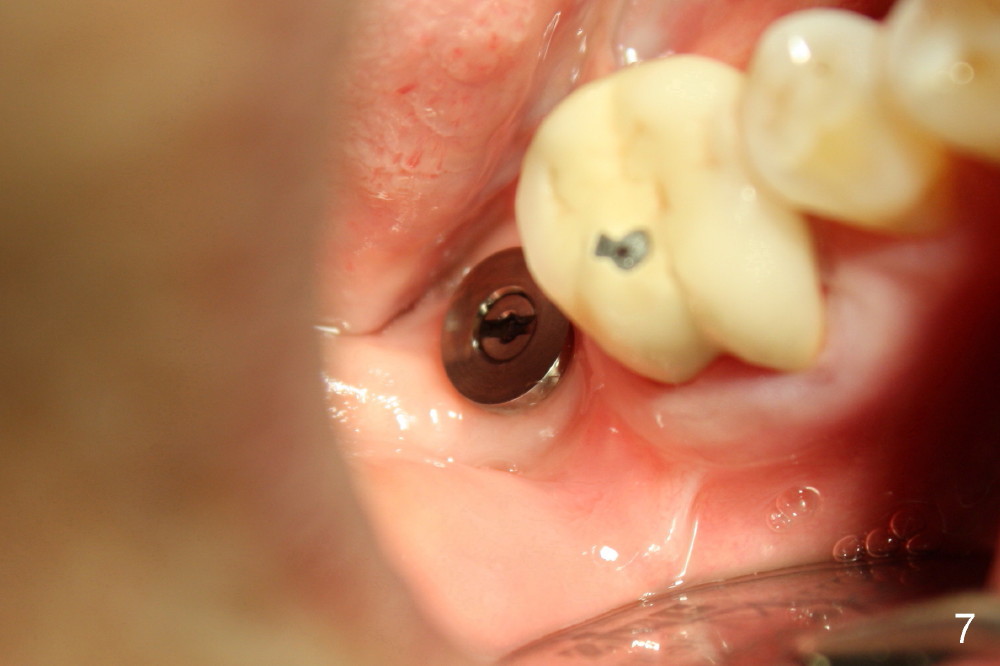

Today the patient returns for implant restoration 4 months after placement. The tissue around the implant is healthy. It appears that there is plenty of clearance (Fig.7). How much I wish no gross reduction!

When a 4.5 mm 20 degree short unipost is engaged into the implant, it touches the opposing tooth (Fig.8). The unipost has to be cut (Fig.9). It takes at least 5 minutes to finish. Finally there is enough clearance for crown (Fig.10). This is my first experience to cut the unipost. The good thing is that I learn the shortened unipost does not seem to affect retention of crown.